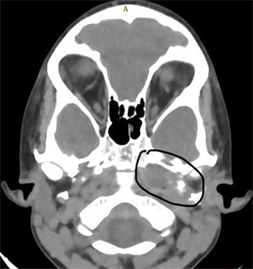

A 4-year-old boy came to our hospital with complaints of Ear ache, purulent discharge, bleeding from left ear since 1 month. Also noticed a mass in left ear since 20 days. He developed left facial paralysis since 1week and diplopia since 3 days. He was treated with antibiotics for 3 weeks elsewhere with no response instead his symptoms got worse after which he was asked to visit a higher centre. On physical examination, there was a polypoid, reddish and fragile mass that filled the external ear canal in the left side, facial nerve palsy (Figure 1(a)), Diplopia (Figure 1(b)) and there was foul smelling discharge from the ear canal. Biochemistry tests were normal. In CT Temporal Bone scan, soft tissue density was present in the mastoid and middle ear. The mass involved the external ear and projected from external auditory meatus. Permeative osteolytic destruction of petrous apex, left carotid canal (Figure 2). Reported as left acute otomastoiditis with petrous apicitis. MRI Brain was normal.

Figure 2. HRCT Temporal bone images. The mass involving external auditory canal, middle ear and mastoid. Permeative destruction of petrous apex and left carotid canal can be seen.